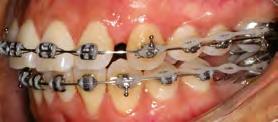

52 | SONRIENDO AL FUTURO

Tratamiento ortodóncico en paciente adulto tratado con extracciones de primeros molares permanentes. Reporte de caso

Tratamiento ortodóncico

en paciente adulto tratado con extracciones de primeros molares permanentes. Reporte de caso